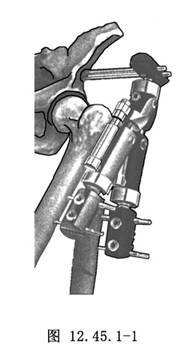

5.牽開器械:選擇帶“T”形夾的單臂外固定架(圖12.45.1-1)。